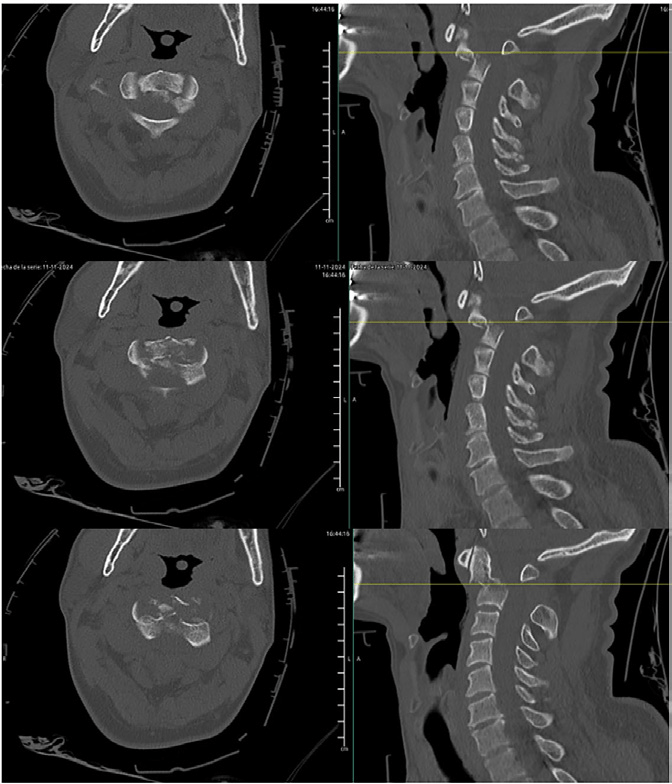

Se realiza TAC cervical donde se objetiva fractura inestable de apófisis odontoides de C2 tipo III de la clasificación de Anderson y D’Alonzo, con desplazamiento de 13,5 mm hacia posterior y disminución del canal raquídeo (tipo IIB según la clasificación de Roy-Camille).

Fractura inestable C2 con desplazamiento y compromiso del canal raquídeo.

Bajo control de escopia, se coloca compás craneal con 2 kg de peso comprobando correcta reducción de la fractura en quirófano.